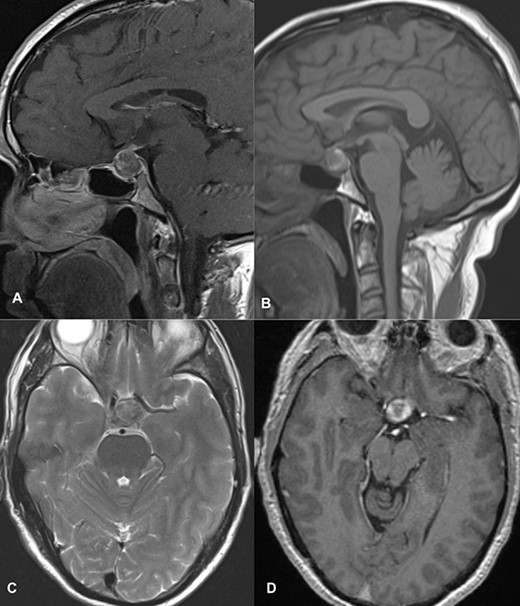

PA was diagnosed when radiographic findings showed acute pituitary hemorrhage and subsequent pituitary adenectomy was planned, but surgery was delayed up to 13 days because of non-critical coronary artery disease detected on coronary angiography. When his condition stabilized, he underwent surgery. The tumor was soft to firm and a safe maximal resection was performed. Hemostasis was achieved and sella packed with fat harvested from the subcutaneous fat of the abdomen. Postoperatively, he suffered transient diabetes insipidus, which was treated with desmopressin injections and resolved by day 5 postoperatively. He was then discharged on the 8th postoperative day. At the time of discharge, he had residual ptosis, which gradually improved over 2 weeks based on clinical assessment at the outpatient visit. He fully recovered from ptosis over a month. Postoperative imaging performed at 6 weeks showed a residual tumor measuring 1.9 × 1.5 × 1.1 cm with no significant mass effect on the cavernous sinus; therefore, he was referred to an oncologist for postoperative radiotherapy (Fig. 2).

Follow-up MRI imaging of case 1 showed the sellar, suprasellar residual lesion measuring 1.9 × 1.5 × 1.1 cm without a significant mass effect on cavernous sinus.